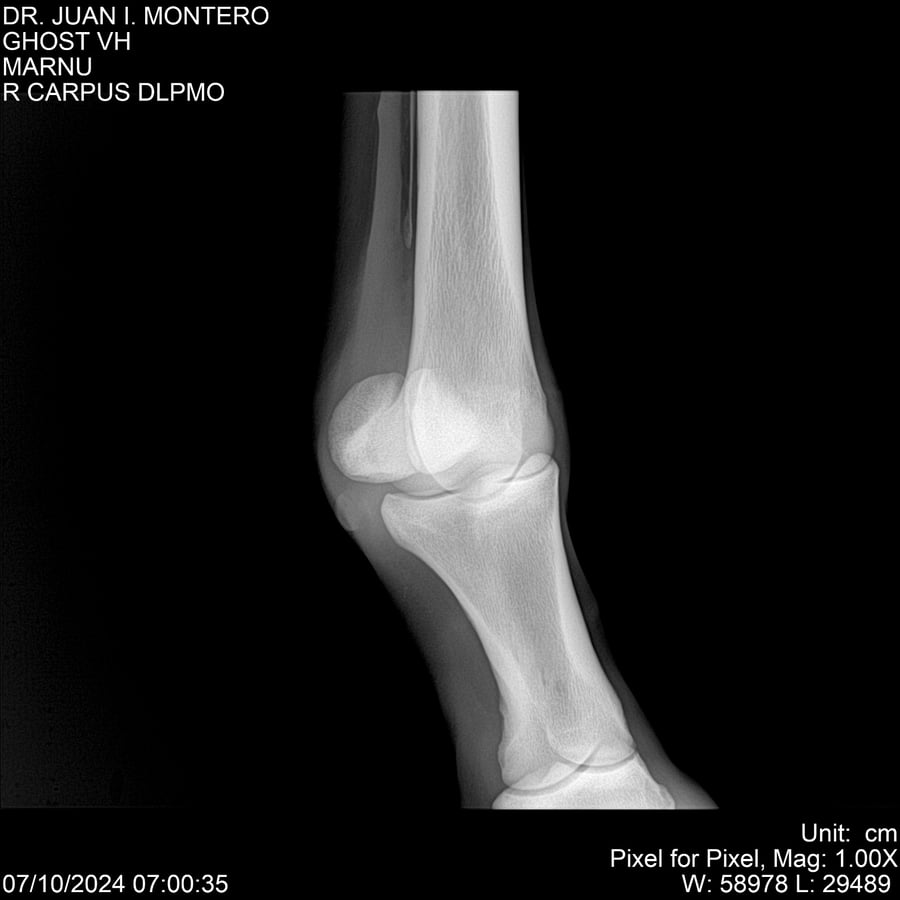

LOTE 15, GHOST VH 🔥 🔥 🔥 Lote Anterior Volver al remate Lote Siguiente Ficha Contacto Montevideo - Ficha del Lote Identificador: #282525 Categoría: Yeguarizos Montevideo - 69 Visualizaciones ClicData Contacto Empresa: Abelenda N. R., Walter Hugo Nombre*: Teléfono* : E-mail* : Mensaje Enviar Registrese gratis Este contenido Exclusivo está disponible sólo para usuarios registrados Ingresar